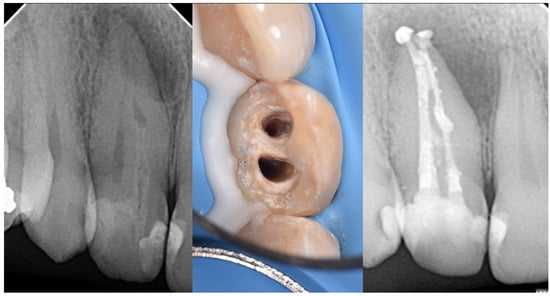

| Type II | Moderate to high risk of pulp involvement | CBCT recommended to assess depth and pulp communication | Preventive sealing or minimally invasive restoration If pulp compromised, vital pulp therapy or root canal treatment depending on health state of pulp | Good to fair prognosis if depth is within coronal third and detected early Radiographic follow-up needed to monitor healing |